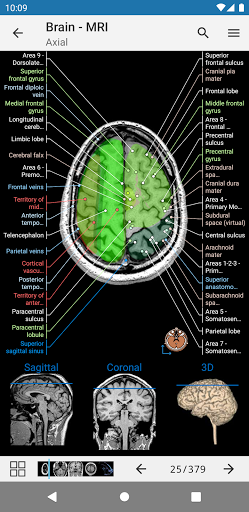

e-Anatomy tiene más de 26 000 imágenes que contienen series de imágenes en vistas axiales, coronales y sagitales, así como radiografías, angiografías, imágenes de disección, gráficos anatómicos e ilustraciones. Todas las imágenes médicas fueron etiquetadas cuidadosamente, más de 967 000 etiquetas disponibles en 12 idiomas, incluida la Terminologia Anatomica latina.

- Desplácese por los conjuntos de imágenes arrastrando el dedo

- Acerque y aleje el zoom

- Toque las etiquetas para mostrar las estructuras anatómicas

- Seleccione las etiquetas anatómicas por categoría

- Localice fácilmente las estructuras anatómicas gracias a la búsqueda de índice